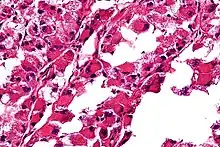

Micrograph of an alveolar soft part sarcoma, showing the characteristic alveolar-like architecture and cells with eccentric nuclei and abundant eosinophilic cytoplasm. H&E stain.

• The term alveolar comes from the microscopic pattern, visible during the analysis of slides of ASPS under the microscope in histopathology. The tumor cells seem to be arranged in the same pattern as the cells of the small air sacks (alveoli) in the lungs. However, this is just a structural similarity. ASPS was first described and characterized in 1952.[1]

ASPS' histomorphologic features include an alveolar-like pattern at low magnification and the presence of large cells with abundant eosinophilic cytoplasm and eccentric nuclei. Calcifications are commonly present, as may be seen with slow-growing neoplasms.